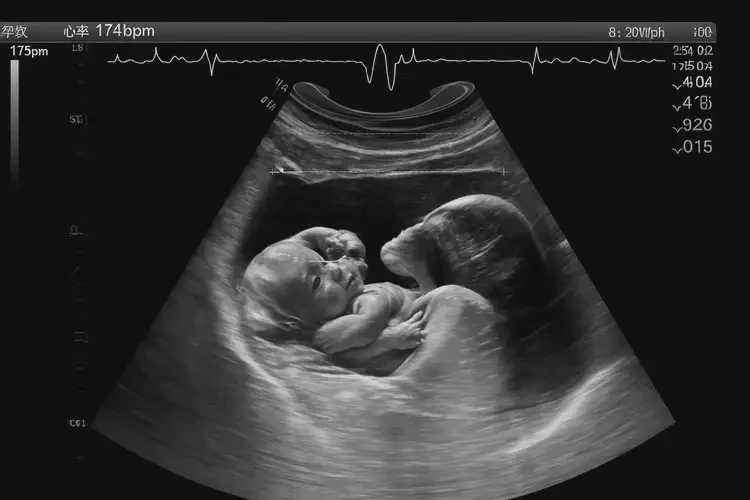

孕25周胎心率174寶寶還能要嗎

胎心率174次/分鐘在孕25周屬于正常范圍,寶寶可以要。

胎心率是指胎兒心臟每分鐘跳動(dòng)的次數(shù),是評(píng)估胎兒健康狀況的重要指標(biāo)之一。在孕25周時(shí),胎兒的胎心率通常在120-160次/分鐘之間。雖然174次/分鐘略高于正常范圍,但并不意味著胎兒有問題。以下是詳細(xì)解釋:

孕25周胎心率174寶寶還能要嗎(圖1)